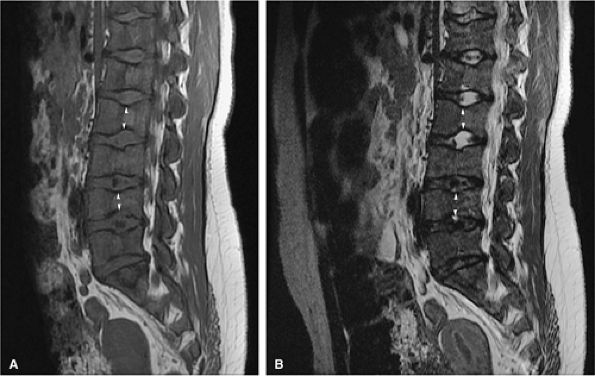

FIGURE 13.16 ● Marrow response to chemotherapy. T1-weighted images of the lumbar spine before chemotherapy (A) and after chemotherapy (B) for metastatic colon carcinoma. Metastatic disease demonstrates low signal intensity at L2 and L4 prior to chemotherapy. High-signal-intensity fatty replacement can be seen after chemotherapy. Adjacent uninvolved vertebral bodies also show a flip-flop in signal intensity as the red marrow is activated.

|